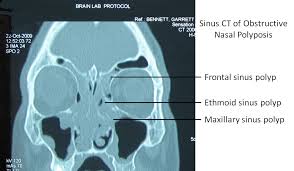

Broadly defined, nasal polyps are abnormal lesions that originate from any portion of the nasal mucosa or paranasal sinuses. The symptoms of nasal polyps are much like symptoms of a cold that doesn't go away, including a stuffy or runny nose. Clinical symptoms and total nasal endoscopic polyp score were evaluated before, 6 years and 12 years after surgery. These benign tumors are small sacs that can appear inside the nose or the sinuses. Many people with nasal polyps can have their symptoms controlled with.

They're made up of inflamed tissues, and can grow to be large. Many people with nasal polyps can have their symptoms controlled with. Oftentimes it's hard to distinguish between symptoms caused by the polyps and symptoms related to the chronic rhinitis that polyps can cause. The most common symptoms they cause are a stuffy, runny nose. They help clear blocked nasal passages and runny nose. They often occur in the area where the upper sinuses drain into your nose (where your eyes, nose, and cheekbones polyps can grow large enough to block your nasal passages, resulting in chronic congestion. Polyps are the most common expansile lesions of the nasal cavity 8. They line the inside of your nose or your sinuses.

A weak immune system or taking drugs that weaken the. Natural treatment for sinus (nasal) polyps involves using a holistic approach to boost the immune system and shrink polyps. Sinus infection (sinusitis) is often confused with rhinitis, a medical term used to describe the symptoms that accompany nasal inflammation and irritation. Nasal polyps (epos) 2012 adalah inflamasi hidung dan sinus paranasal ditandai dengan dua gejala atau lebih chronic rhinosinusitis (crs) is a sinus paranasal and nasal inflammation marked with two or more symptoms, nasal congestion or nasal discharge and the other symptom like facial. Nasal steroid sprays shrink polyps. Nasal polyps are benign (noncancerous) growths that may form inside nasal passages and sinuses — the spaces behind your nose and cheeks. Nasal polyps can develop on either or both sides of the nose. Clinical symptoms and total nasal endoscopic polyp score were evaluated before, 6 years and 12 years after surgery. When to seek medical care. Symptoms include trouble breathing through the nose, loss of smell, decreased taste. This inflammatory disease of the nose and paranasal sinuses with nasal polyps (np) accounts for substantial health care expenditures in terms of office visits, antibiotic prescriptions. It has also reduced the mucus in the sinus. While the term 'growth in the nose or sinus' seems serious, nasal polyps are not cancerous tumors but may sometimes occur in cases of neoplasms of the nose or paranasal sinuses.